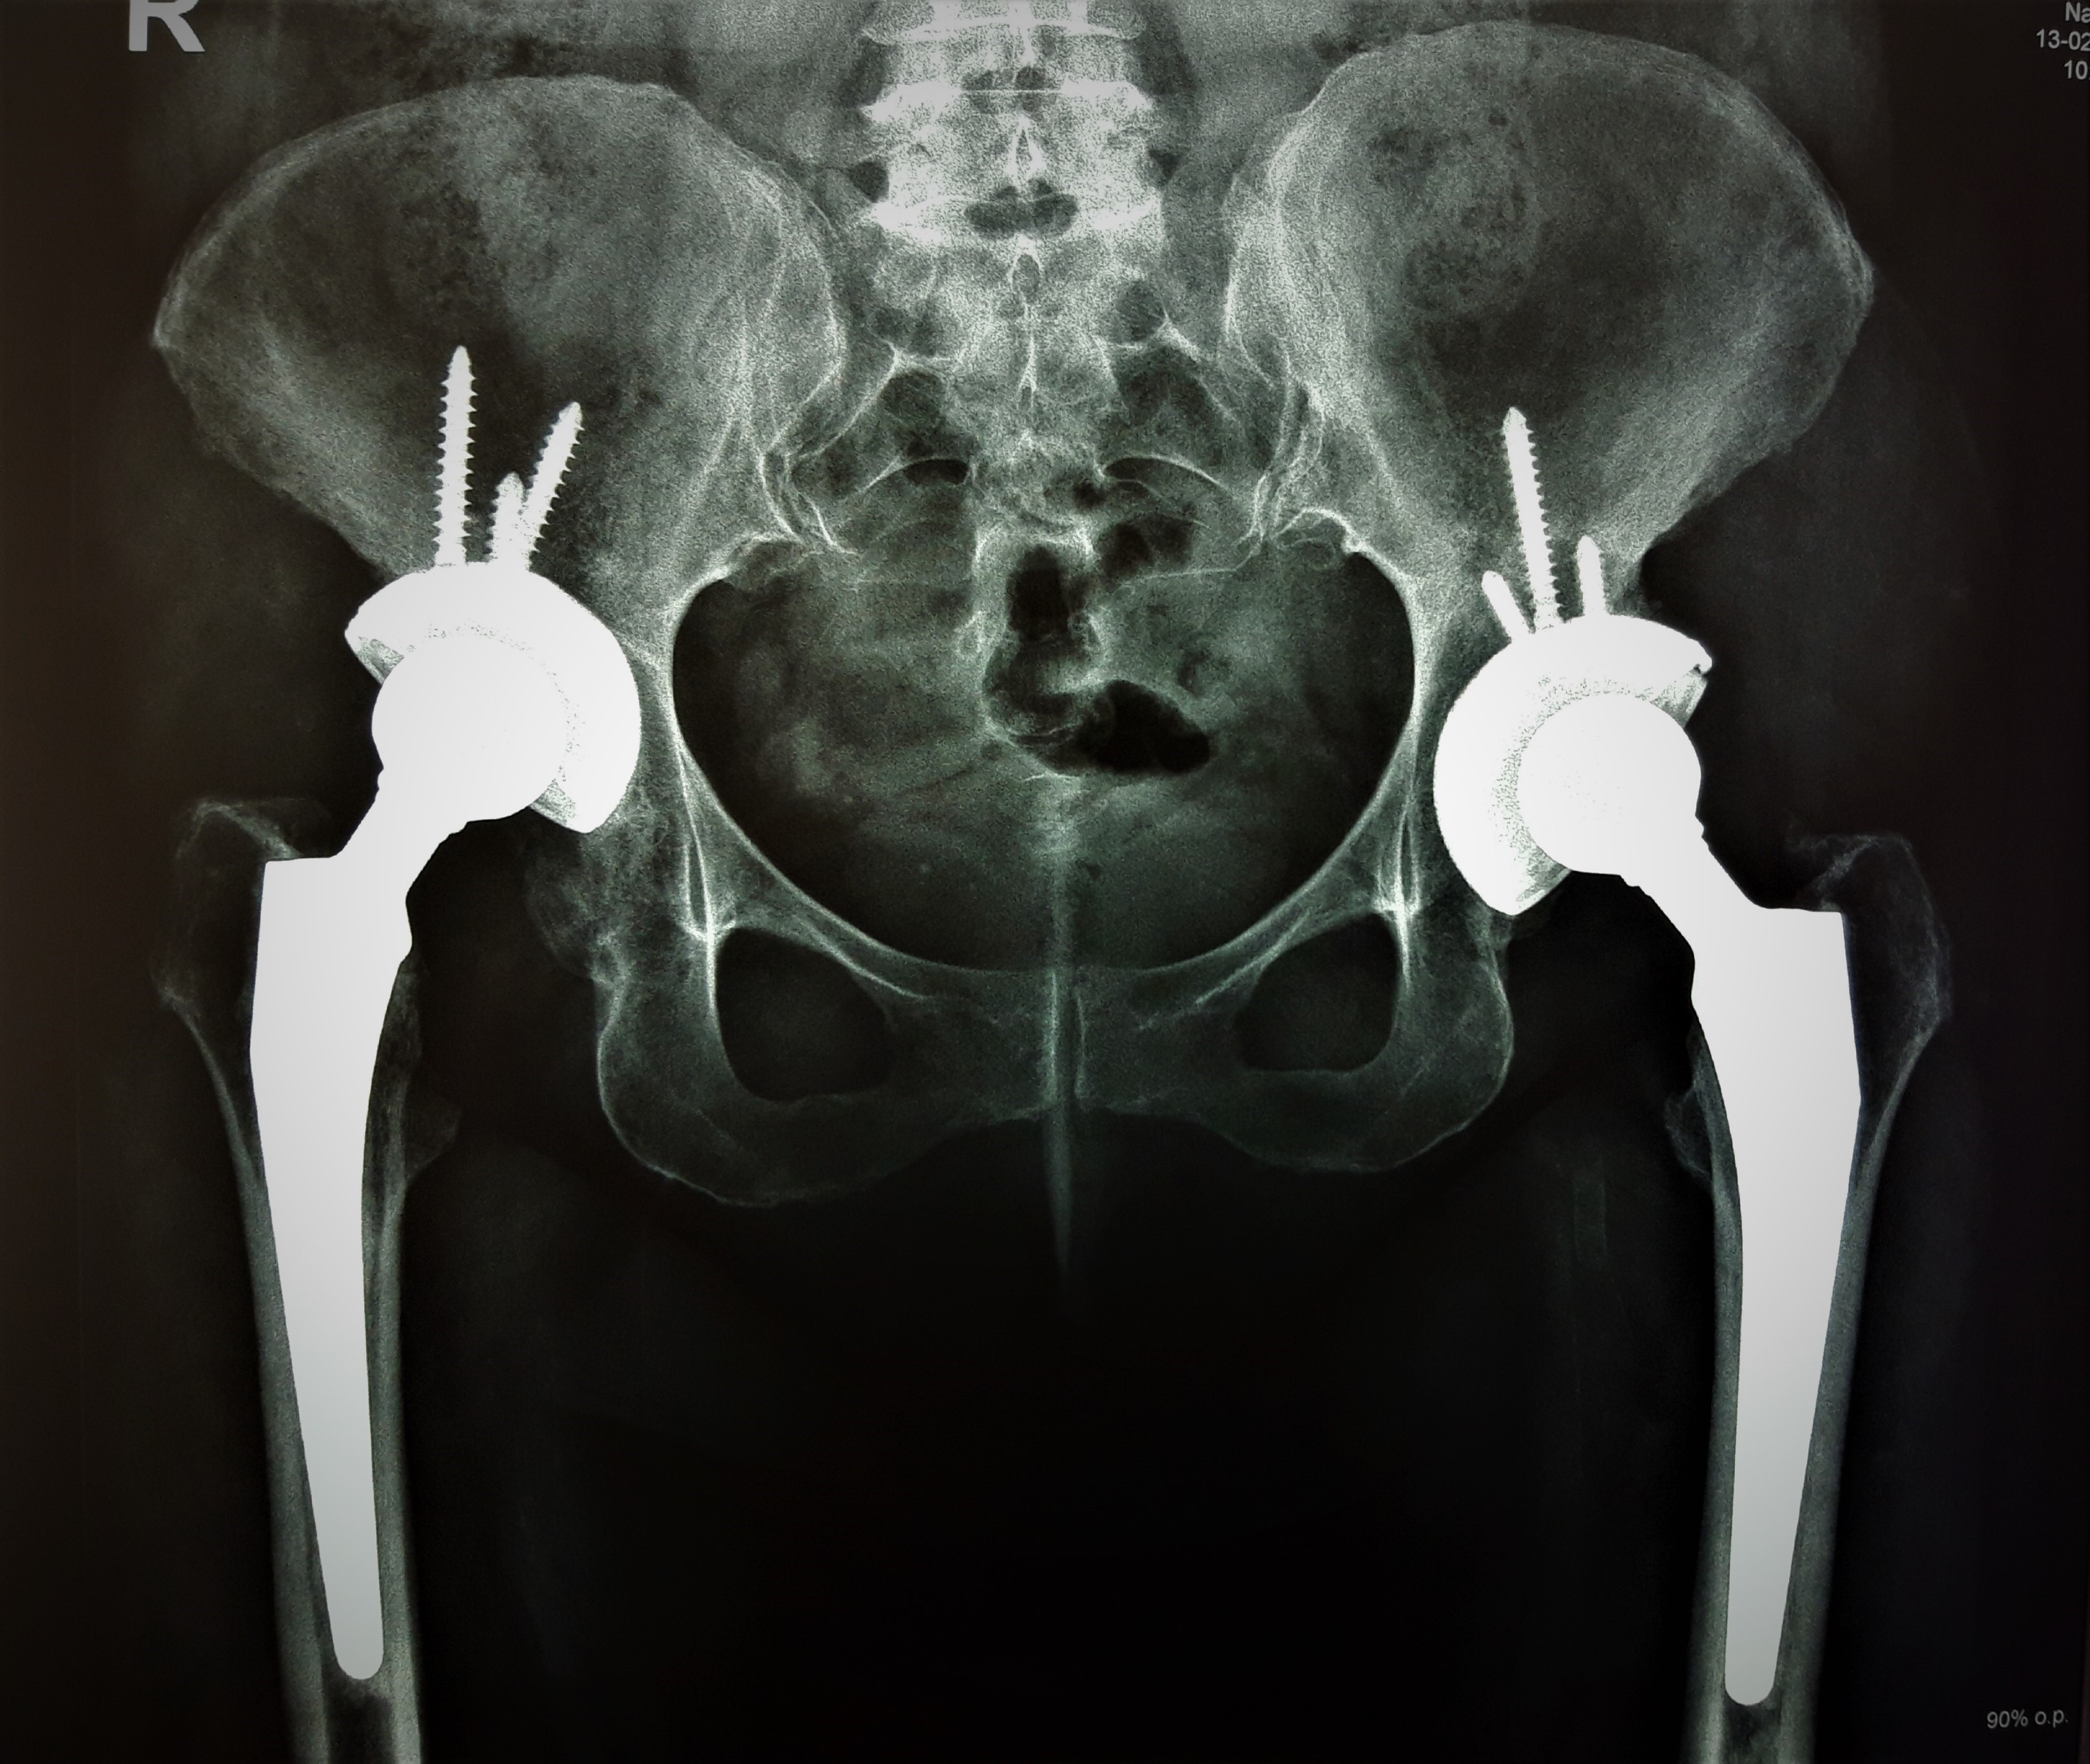

նկար 1․ Նախքան վիրահատությունը նկար 2․ Վիրահատությունից 7 տարի անց